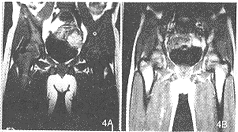

急性白血病组: T1WI: (1)治疗前组38例:腰骶椎38例所有椎体均表现为均匀的信号降低,比相邻的椎间盘和脊髓的信号均明显降低;髂骨38例均表现为低信号,其中3例于髋臼旁见斑片状高信号残留;股骨近段信号降低38例,其中8例股骨头、股骨大转子见斑片状高信号残留,且此8例均有骨骺板存在。 (2)化疗缓解组25例:所有椎体、髂骨、股骨头、股骨大转子及骨干均表现为不同程度的信号增高,达完全缓解者(21例)比部分缓解者(4例)更接近相应的正常骨髓信号(图3、4)。其中9例还作了治疗后追踪观察,第1次为化疗1疗程结束5天内并经临床及骨髓穿刺认为完全缓解时行MRI检查,第2次为2~4周内经骨髓穿刺后行MRI检查。6例2次经骨髓穿刺检查均为完全缓解,但第2次MRI检查椎体信号比第1次略为增高(图5)。复发的3例中,2例再次缓解,经MRI检查,其骨髓信号重新升高。

图3 男,11岁。急性白血病。T1WI示:A.治疗前椎体呈均匀低信号,椎体形态正常;B.治疗后完全缓解其椎体信号明显升高 图4 同图3病例。T1WI示:A.治疗前髂骨、股骨上段信号明显降低;B.治疗后完全缓解其信号升高 图5 17岁。急性白血病。T1WI示:A.治疗前椎体均匀低信号;B.治疗后缓解2天,椎体信号稍升高;C.治疗后缓解3周,椎体信号明显升高